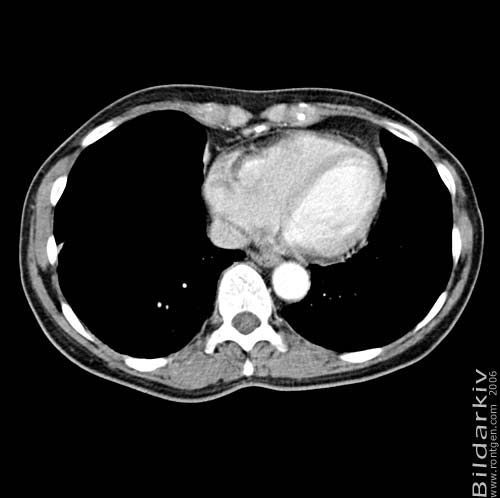

Thorax 42

Snitt över thorax med kontrast. Sk. mediastinum-fönstersättning.

CT Röntgen Helsingborgs lasarett

Mediastinum